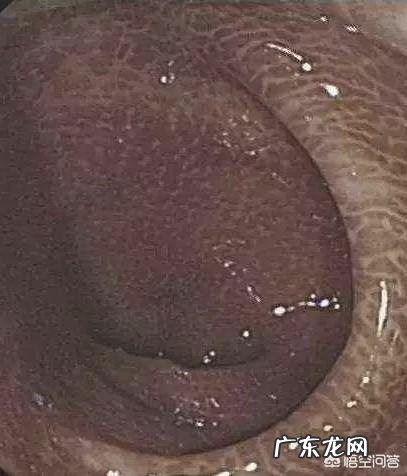

【为什么经常吃泻药肠子变黑了?】

“肠变黑”是一种以大肠粘膜色素沉着为特征的非炎性肠病,缺乏特异的临床表现,多在做肠镜时发现 。长期服用刺激性泻药,大黄、芦荟、番泻叶、决明子等蒽醌类中药属于刺激性泻药,损伤肠壁神经丛和粘膜细胞坏,进而影响正常的肠道蠕动和生理节律 。最终形成药物依赖,进一步加重便秘程度,同时坏死的粘膜细胞脱落或被吞噬,导致肠粘膜变黑 。对于肠已变黑的患者需立即停用蒽环类泻药,多可以恢复至正常颜色 。